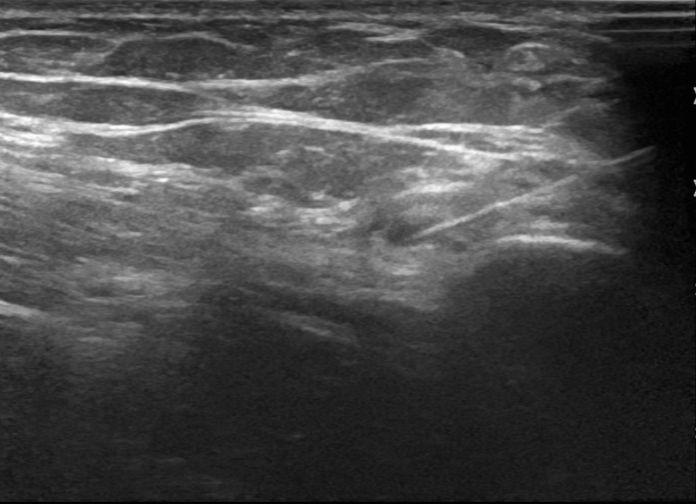

3. Injection of lateral femoral cutaneous nerve for meralgia paraesthetica